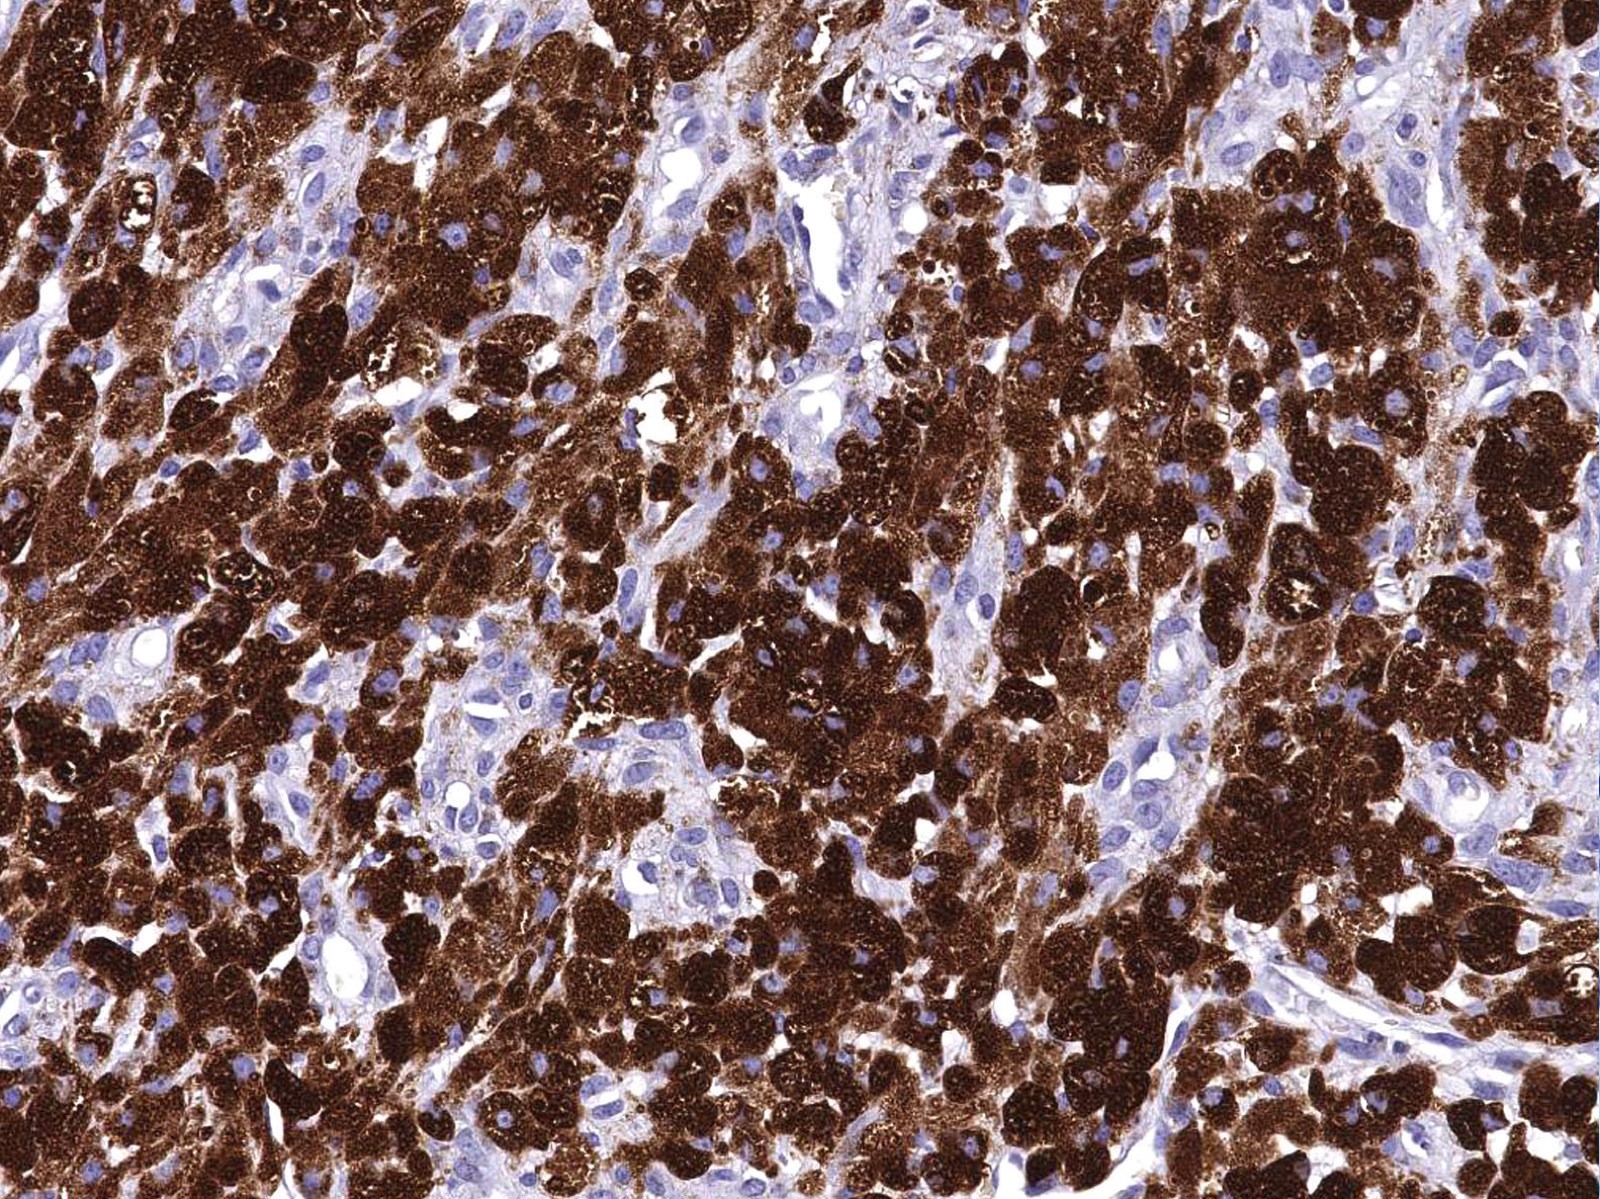

Microscopic (histologic) images

Contributed by Jarish Cohen, M.D., Ph.D.

Positive stains

- PASD, Sudan Black B, S100 (except for nonneural granular cell tumors), SOX10, NSE

- Variable staining for vimentin, CD68, NKI-C3 (CD63), MITF, CD56

- A subset of nonneural granular cell tumors express ALK

- References: Cancer 1982;49:1624, Histopathology 2012;61:997, Diagn Histopathol 1982;5:205, Cancer 1989;64:1455, Dermatology 1993;186:106, Am J Dermatopathol 2007;29:22, Hum Pathol 2015;46:813, Am J Surg Pathol 2018;42:1133